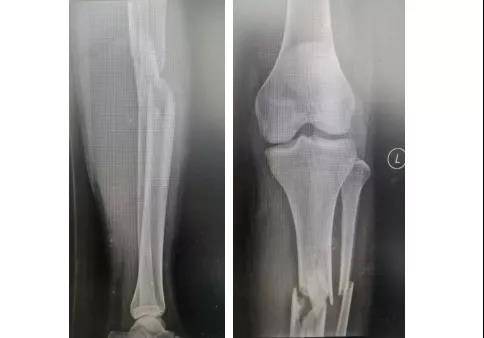

X光片显示 , 患者左胫骨近端粉碎性骨折 , 左腓骨骨折 。 因骨折情况严重 , 局部肿胀明显 , 该院骨科主任郭树章判断患者有出现“骨筋膜室综合征”的危险 。

为让患者得到更好的治疗 , 郭树章主任与副主任医师李晓东 , 主治医师冯凤辉、刘绍铭进行了严谨的术前讨论 , 认为传统入路髓内钉容易导致骨折近端向前成角及向内成角 , 且在术中难以维持稳定 , 决定为患者实施髌上入路髓内钉治疗 。